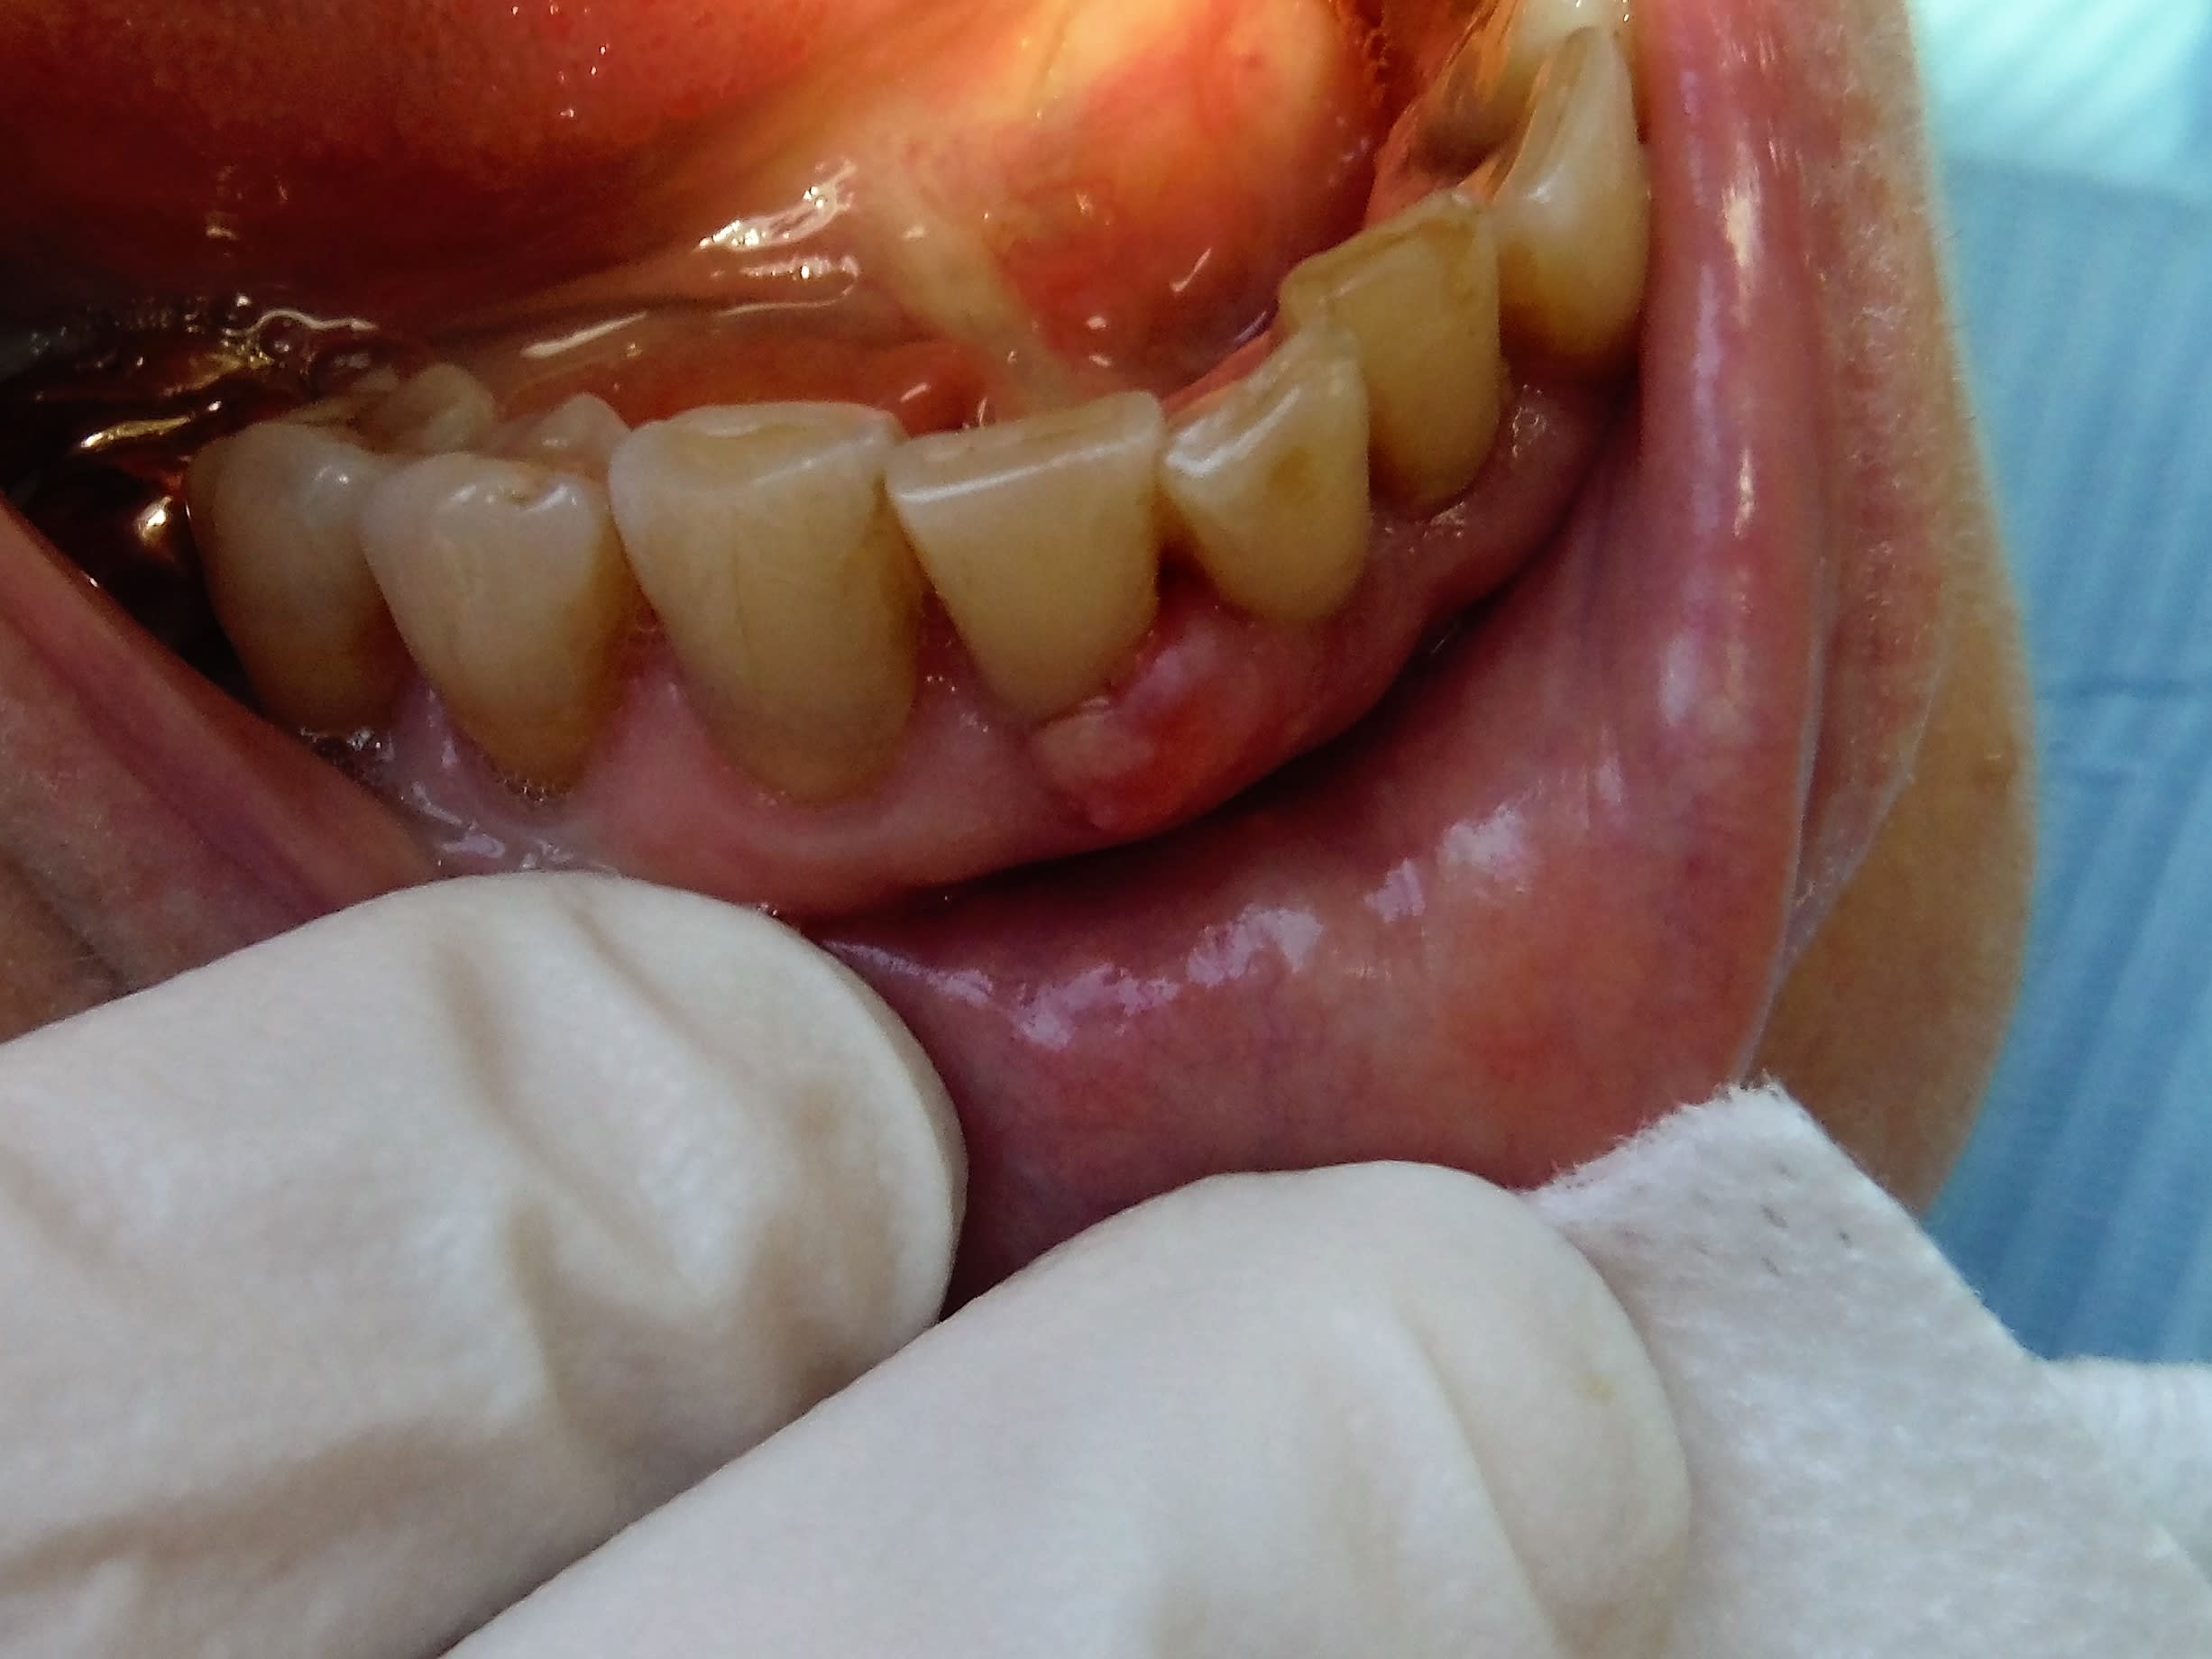

Bonjour a tous, j'ai besoin de vos lumières à nouveau. Jai reçu ce patient ce matin, il s est réveillé avec ca mercredi matin. Depuis la couleur est passé du très foncé au violacé. Douleur à la palpation ou à l effleurement, il n'ose plus brosser. Rx faite , pas de carie radiculaire, pas de lipoe. J avais pensé à un epuli quand il m.a appelé, mais finalement ça n y ressemble pas vraiment. Et ça ne saigne pas au contact contrairement à l epulis. Bref. Si ça parle à qqn.....merci

j'ai déjà vu des epuli ca ny ressemble pas tout a fait mais surtout c est douloureux a l a palpation et ça ne saigne pas contrairement a l l'epulis

Au niveau paro, ça semble pas top avec un fond de GUN et sur Lyon

Ben sur la photo, entre 11et 12, collet 44 et saignement 41 42, ça ressemble bien à une GUN ou gingivite agressive comme tu veux...

Après, vu la quantité de plaque en inter dentaire, je suis pas étonné du résultat. Système immunitaire ???